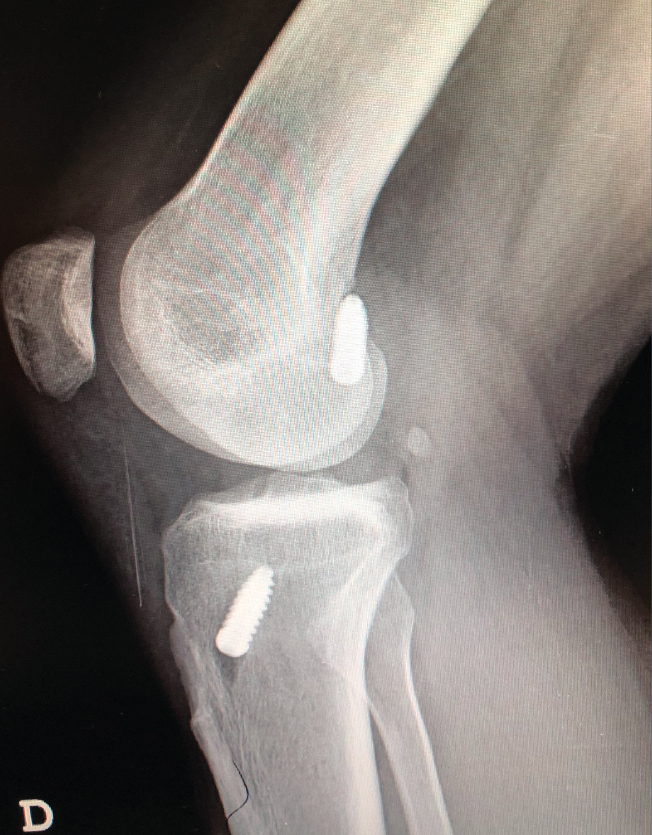

La literatura ha identificado diferentes grupos de riesgo altamente expuestos a un fracaso de la cirugía del LCA. Pacientes hiperlaxos, mujeres jóvenes o con una alta demanda funcional (deportes de pivotaje) tienen cifras mayores de fracaso(10,12). El estudio detallado de estos casos, así como la identificación de posibles factores agravantes –pendiente tibial(13), eje mecánico varo-valgo, escotadura intercondílea estrecha(14)(Figura 4)–, pueden hacer necesario añadir gestos quirúrgicos correctores, como son la osteotomía tibial, el remodelado de la escotadura intercondílea o una plastia extraarticular de refuerzo (Figura 5).

Figura 4. Escotadura intercondílea estrecha. Forma de “catedral gótica”.